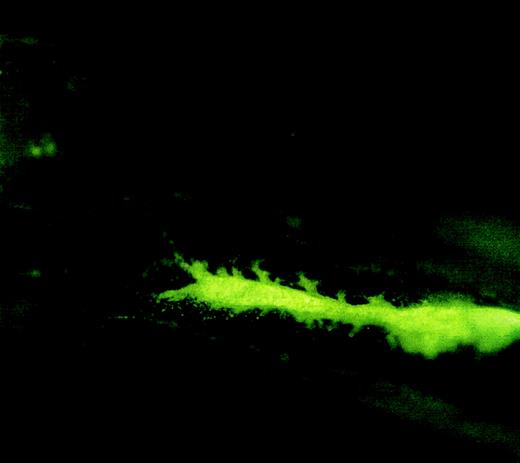

The following experiments were performed to ensure that the donor cells were not injected into the bloodstream. First, 5 minutes after implantation, the implanted femur was removed and examined under a fluorescence microscope. As shown in Figure2, donor cells (CFSE labeled) are concentrated within the femur cavity. Second, donor cell concentration in the bloodstream was analyzed and compared between the mice that received implantation and the mice that received traditional tail vein infusion.

Fluorescence microscopic picture of a femur longitudinal section showing the location of injected cells in the femur cavity.

Lin− cells were labeled with carboxyfluorescein diacetate, succinimidyl ester (CFDA) and injected into a femur cavity by a 26-gauge needle. The needle insertion hole was sealed with bone wax. The mouse was killed 5 minutes after injection, and the injected femur was removed for fluorescence microscopic analysis. Original magnification, 2 × 20.